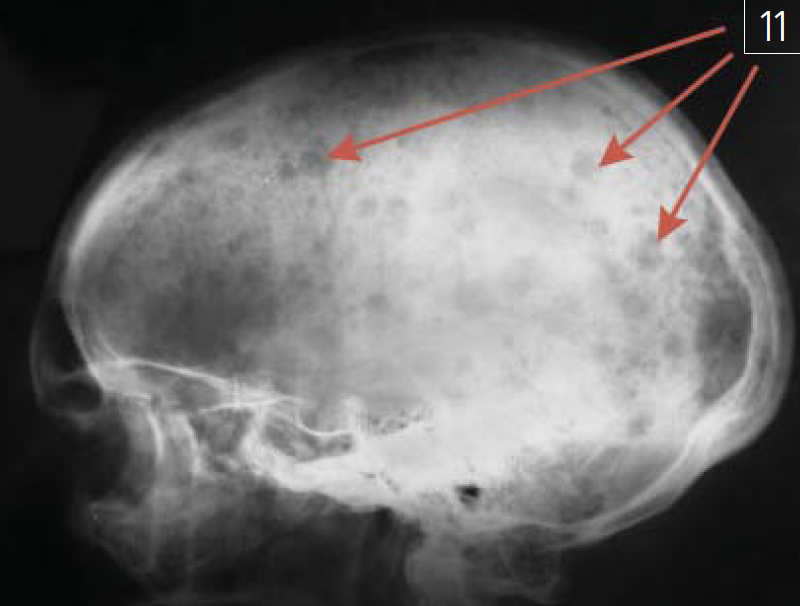

Миеломная болезнь (множественная миелома, генерализованная плазмоцитома, болезнь Рустицкого-Калера) — злокачественная опухоль из плазматических клеток (дифференцированных В-лимфоцитов, пропуширующих антитела). Данное заболевание системы крови, относящееся к парапротеинемическим лейкозам, рентгенологически характеризуется четко очерченными "штампованными" очагами деструкции различной величины в костях свола черена, ключинах, ребрах, костях таза (рис. 11).

Рис. 11. Участки деструкции в костях свода черепана рентгенограмме костей мозгового черепа в боковойпроекции (указаны красными стрелками) при миеломнойболезни